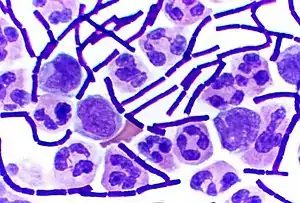

Color-enhanced scanning electron micrograph shows splenic tissue from a monkey with inhalational anthrax; featured are rod-shaped bacilli (yellow) and an erythrocyte (red) Gram-positive anthrax bacteria (purple rods) in cerebrospinal fluid: If present, a Gram-negative bacterial species would appear pink. (The other cells are white blood cells.)

Gram-positive anthrax bacteria (purple rods) in cerebrospinal fluid: If present, a Gram-negative bacterial species would appear pink. (The other cells are white blood cells.)

Various techniques may be used for the direct identification of B. anthracis in clinical material. Firstly, specimens may be Gram stained. Bacillus spp. are quite large in size (3 to 4 μm long), they may grow in long chains, and they stain Gram-positive. To confirm the organism is B. anthracis, rapid diagnostic techniques such as polymerase chain reaction-based assays and immunofluorescence microscopy may be used.[35]